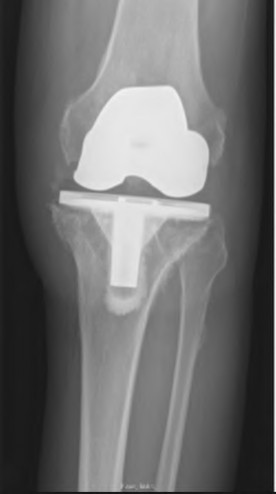

The radiograph demonstrates a periprosthetic femur fracture extending to the tip of the stem. The long spiral fracture is consistent with a loose implant. The bone stock is sufficient. Therefore, this fracture pattern would classify as a B2 using the Vancouver classification system. The Vancouver classification for periprosthetic femoral fractures is simple yet incorporates all the pertinent factors such a location, stem fixation, and bone stock. Type A is a trochanteric fracture- lesser or greater. These can be treated non-operatively usually and ORIF if symptomatic. Type B fractures are around or just below the stem and are subdivided into three types. Type B1 is a fracture with a well fixed stem.

The treatment is cable plating or allograft struts or a combination of the two. Type B2 is a fracture with a loose stem with good bone stock. The treatment is a cementless porous coated long stem atleast two diameter length past the

fracture site. Type B3 is a fracture with a loose stem and comminution. For younger patients, use cementless porous coated long stems with allograft struts. For older patients, consider a tumor prosthesis. Cement fixation is sometimes necessary Type C is a fracture well below the stem tip. These can be treated independently of the prosthesis.